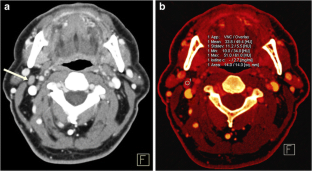

To evaluate whether dual-energy computed tomography (DECT)-derived iodine content and iodine overlay could differentiate between normal, inflammatory and metastatic squamous cell carcinoma (SCC) cervical lymph nodes.

This study was approved by the institutional review board. Sixteen patients with normal lymph nodes, 20 patients with enlarged nodes draining deep cervical inflammations and 23 patients with pathologically proved metastatic SCC nodes who underwent contrast enhanced DECT were retrospectively identified. Iodine content and overlay of 36 normal, 43 inflammatory and 52 metastatic lymph nodes were calculated using circular regions of interest and compared among the three groups. A receiver operating characteristic (ROC) curve was used to determine the sensitivity and specificity of iodine content and overlay for diagnosis of metastatic nodes.

Iodine content (mg/ml) was significantly lower for metastatic lymph nodes (2.34 ± 0.45) than for normal (2.86 ± 0.37) and inflammatory (3.53 ± 0.56) lymph nodes, P < 0.0001. Iodine overlay (HU) was also significantly lower for metastatic lymph nodes (47 ± 11.6) than normal (57.4 ± 8.2) and inflammatory nodes (69.3 ± 11.5), P < 0.0001. The areas under the ROC curve for iodine content and iodine overlay were 0.923 and 0.896.

DECT-derived iodine content and overlay differ significantly among normal, inflammatory and metastatic SCC cervical lymph nodes.